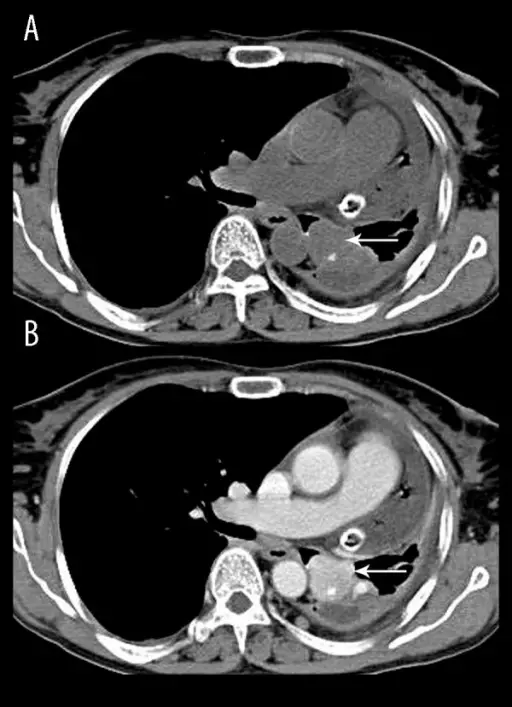

Pheochromocytoma

A particular kind of neuroendocrine tumor (NET) known as a pheochromocytoma develops from chromaffin cells.

Clinical features of pheochromocytoma results from elevated serum catecholamine levels.

- Episodic hypertension

Increased 24-hour urine production and serum metanephrine levels are used to diagnose the disease.

Medical excision is used as a treatment of choice.

When the tumor is manipulated, catecholamines may leak into the bloodstream.

An irreversible alpha-blocker called phenylbenzylamine is given preoperatively to stop a hypertensive crisis.